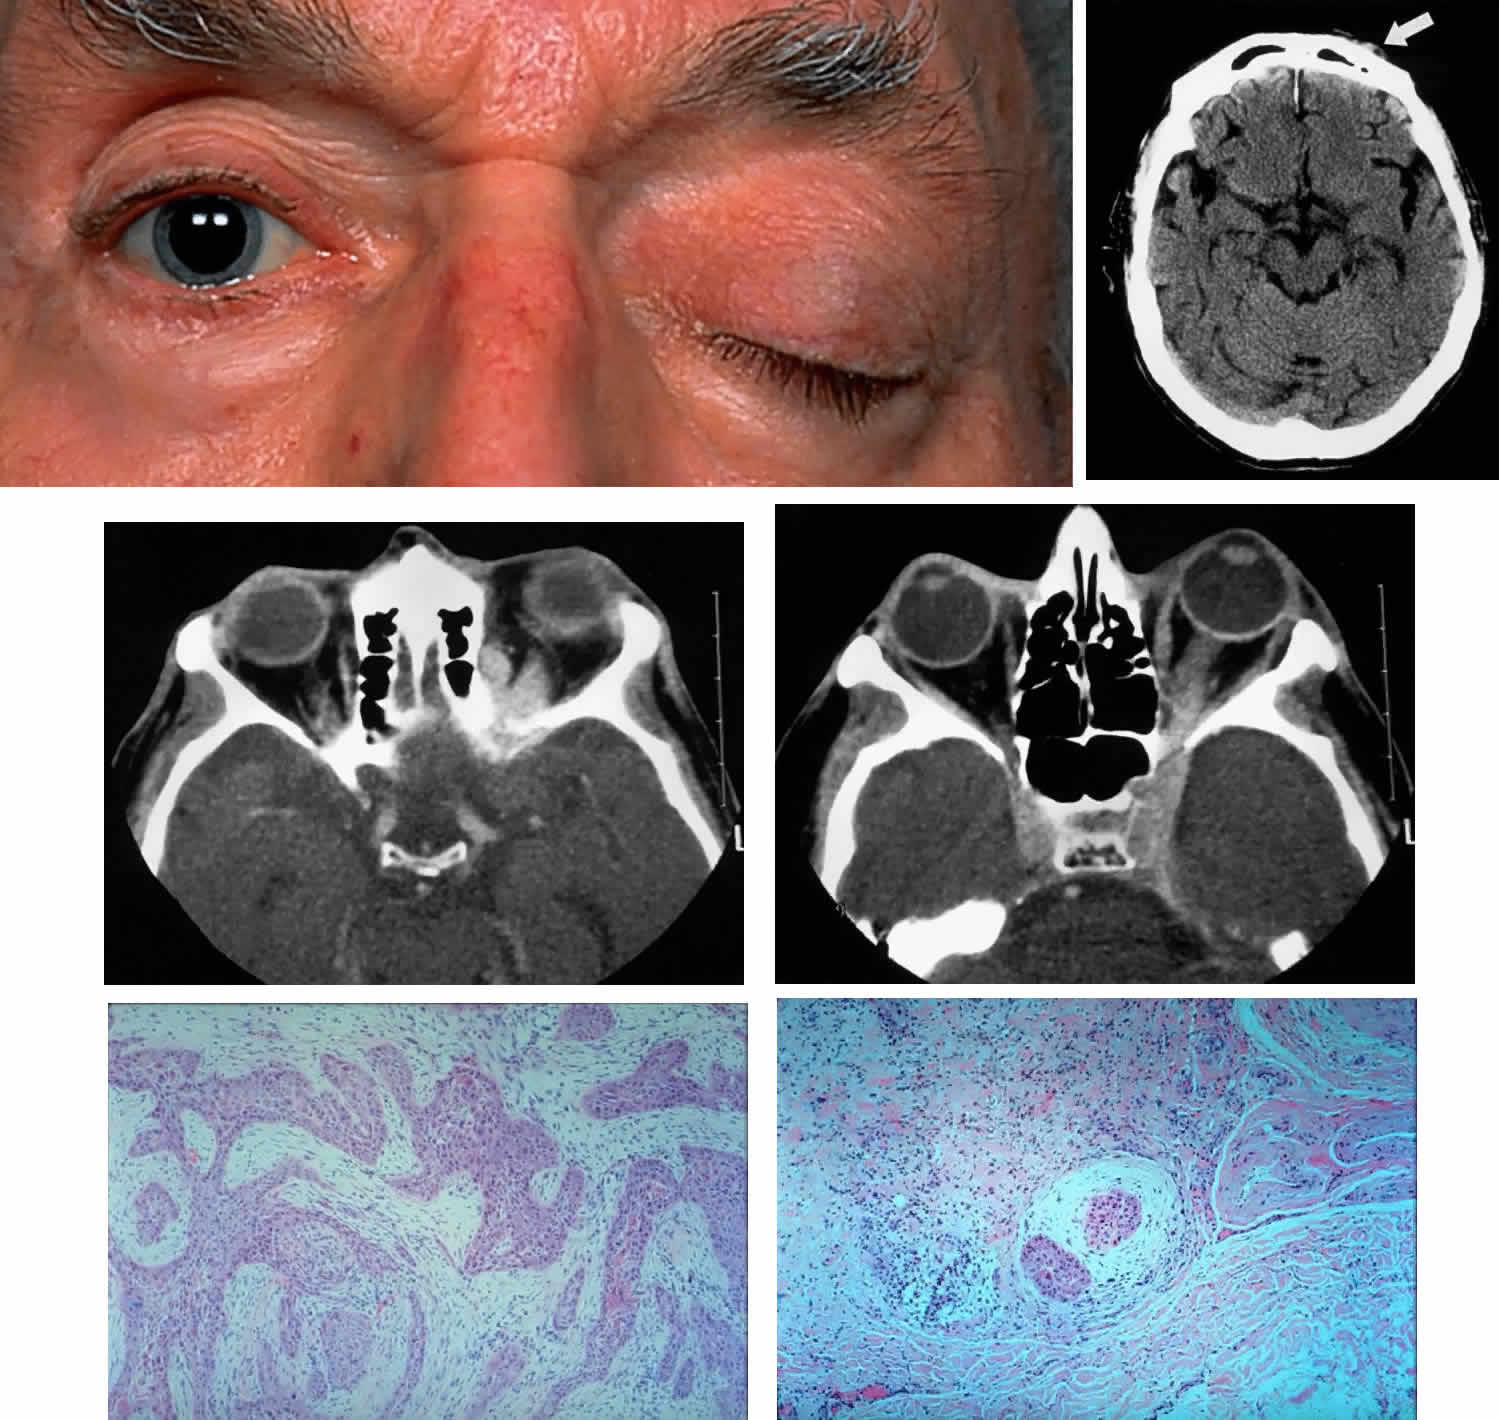

Fig. 8. A 73-year-old man treated 3 years previously with excision of a squamous cell carcinoma in the left supraorbital region had recurrence of tumor, which was again excised. He developed progressive pain and tingling in the forehead, vertical diplopia, and finally general malaise lasting 18 months, ultimately requiring hospitalization. He was treated with corticosteroids for presumed Tolosa-Hunt syndrome, showed minimal improvement, and was discharged. Over a 2-month period, he developed decreased vision, ptosis, and bulging of the eye. On presentation he had vision of 20/80 with a relative afferent pupillary defect. There was hypesthesia in the distribution of cranial nerve V1 and hyperesthesia in V2. He had a palpable fixed cord in the forehead in the distribution of the supraorbital nerve, complete ptosis, ophthalmoplegia, and 7 mm of proptosis (A). CT scan showed local infiltration along the supraorbital nerve (B, arrow), with extension of a soft tissue mass along the orbital roof to the orbital apex (C), through a widened superior orbital fissure, and into the cavernous sinus (D). An orbital biopsy revealed cords of squamous cells (E) (H & E, × 80) and evidence of infiltration inside a small branch nerve sheath (F) (H & E, × 80). A single fraction of 10 Gy was given as palliative treatment for pain control.